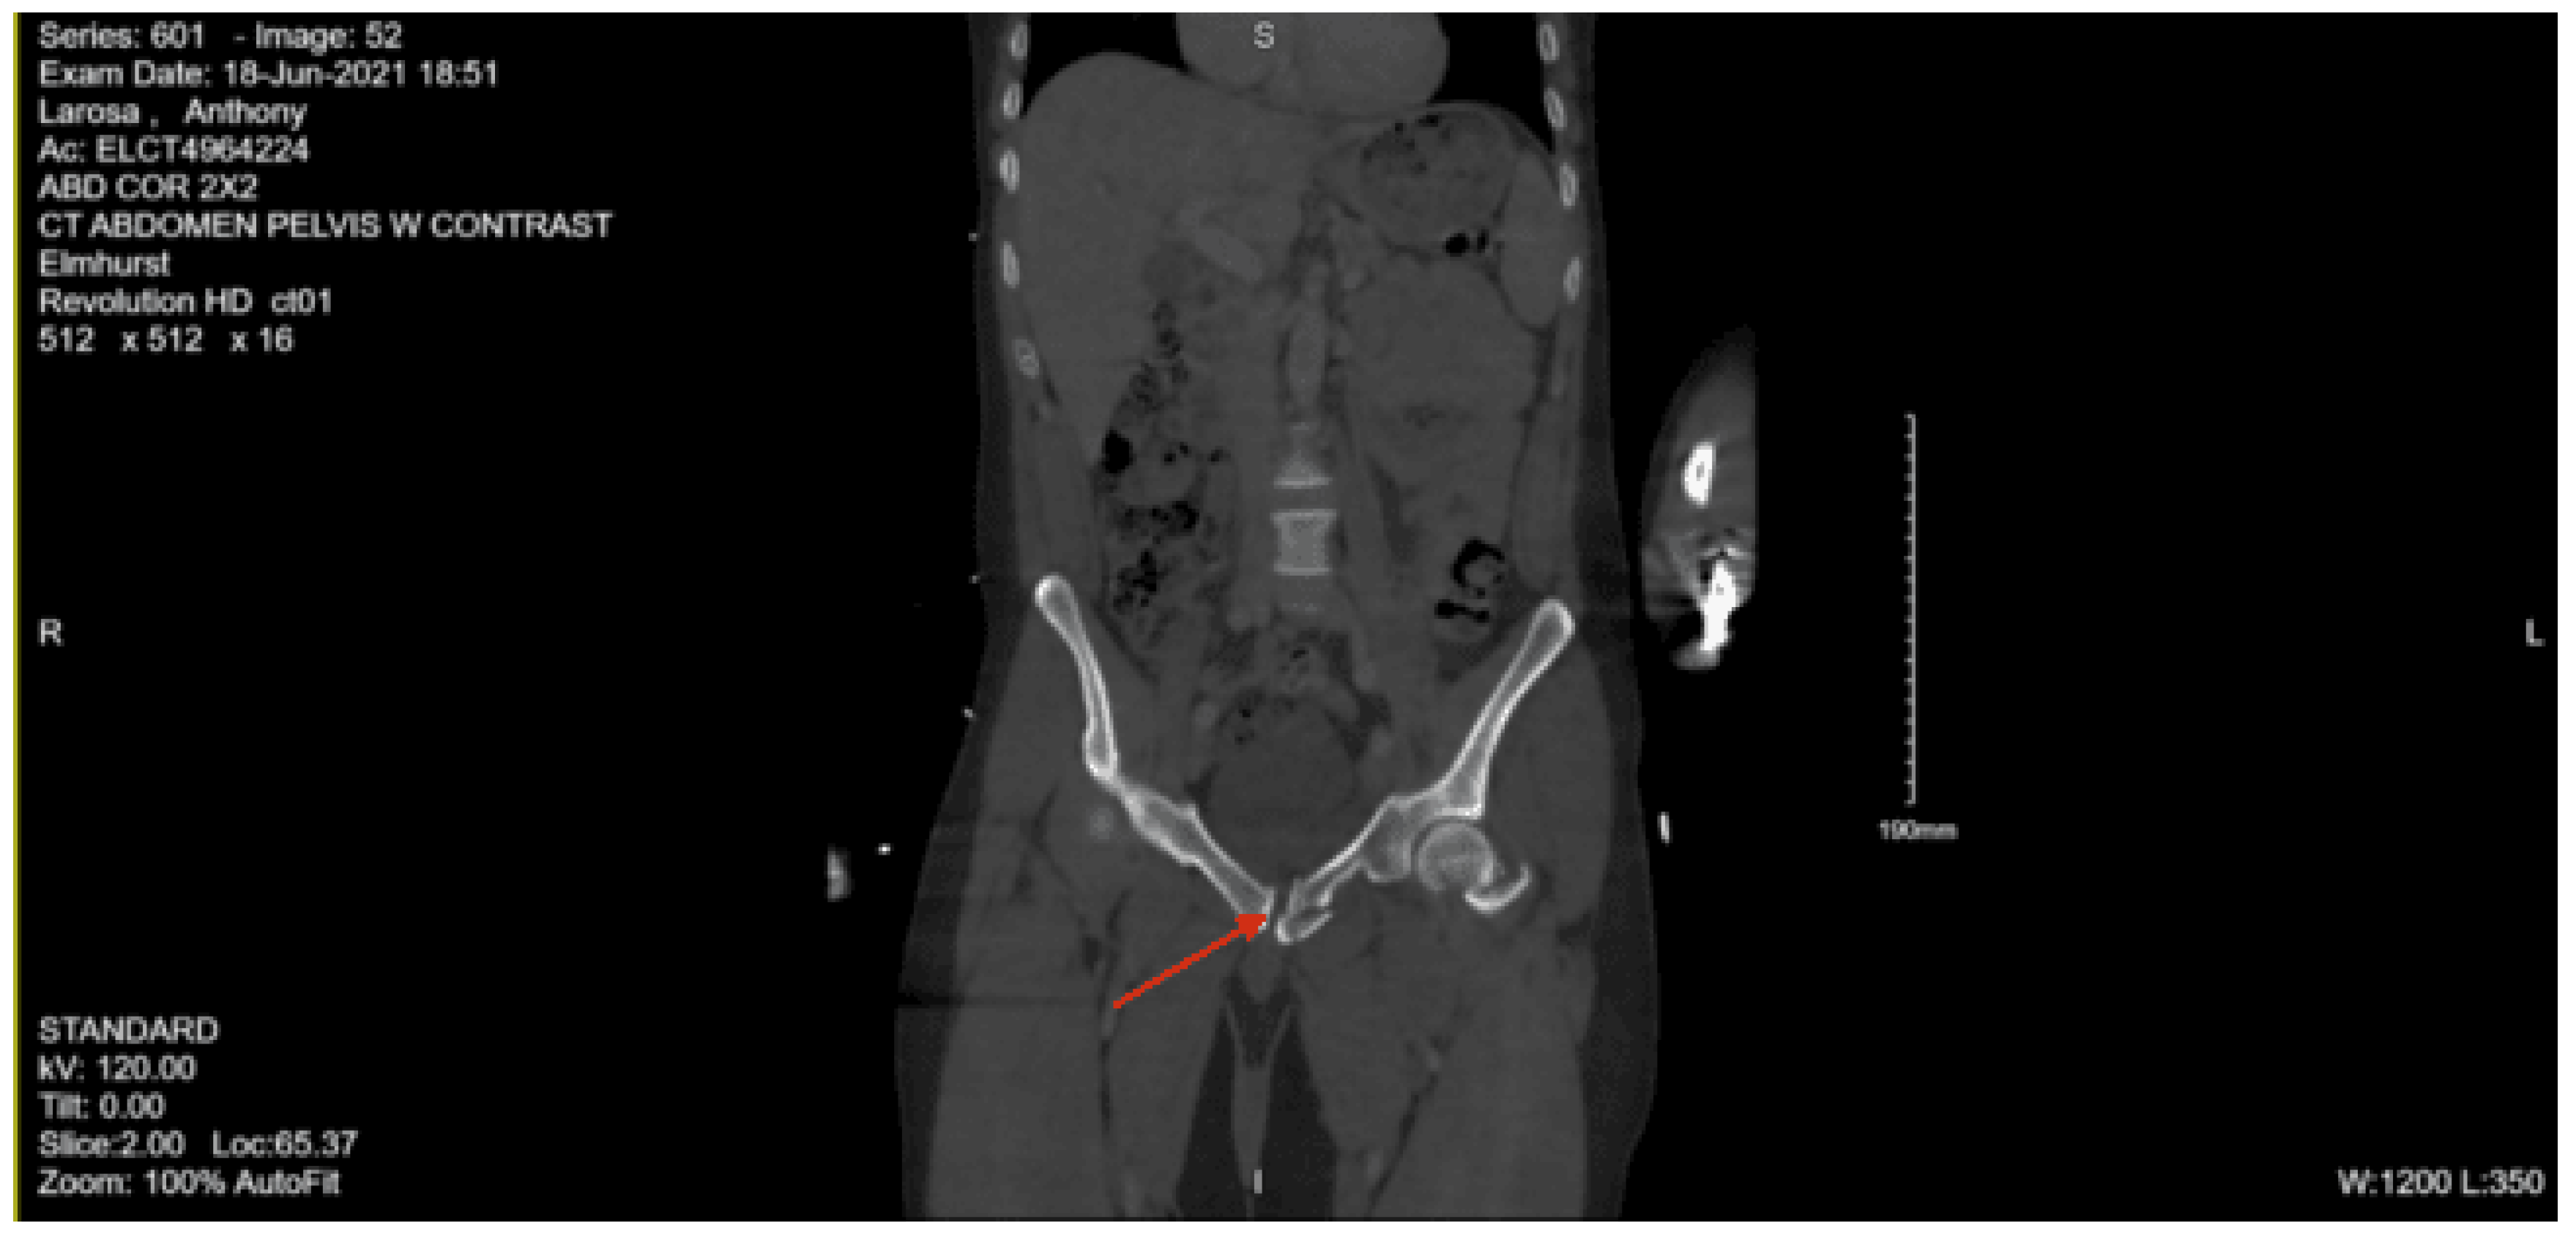

Imaging as shown in Figure 1, Figure 2 and Figure 3:

CT lumbar spine w/o contrast: An acute comminuted fracture is seen involving the superior portion of the left sacral wing. The SI joints are intact. Intact lumbar spine.

CT abdomen/pelvis with contrast: Acute fractures are seen involving the right superior pubic ramus and left inferior pubic ramus. An acute comminuted avulsed fracture of the left sacral wing in the superior and midportion is demonstrated. No definitive acute traumatic visceral abnormalities were found throughout the abdomen and pelvis.

DX: Denis zone II left sacral alar fx involving S1 foramina. AOSpine B3: NX, M3